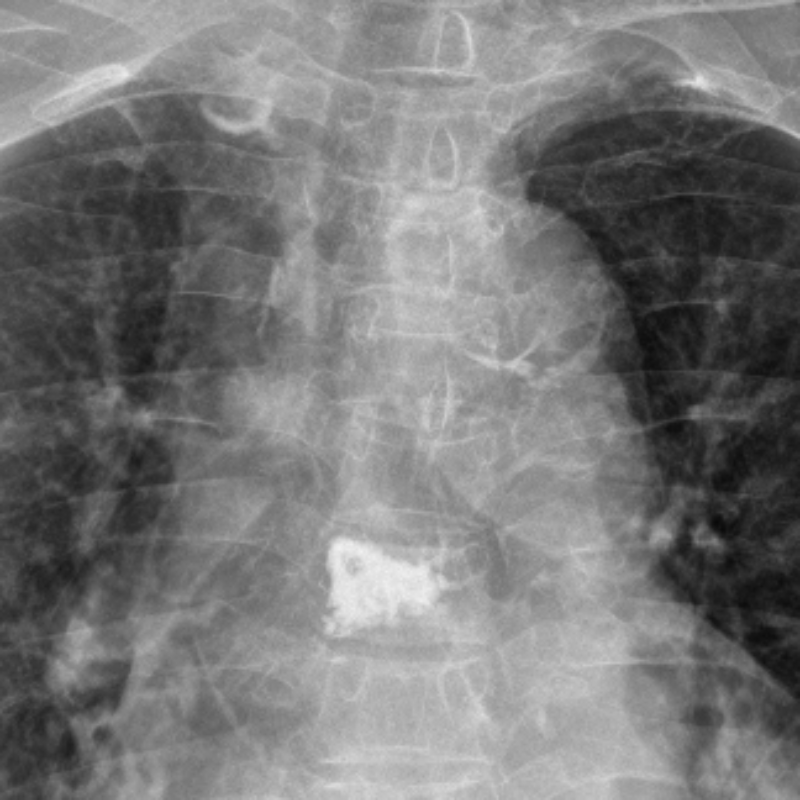

△術后復查胸6、腰3椎體內骨水泥置入狀態良好。